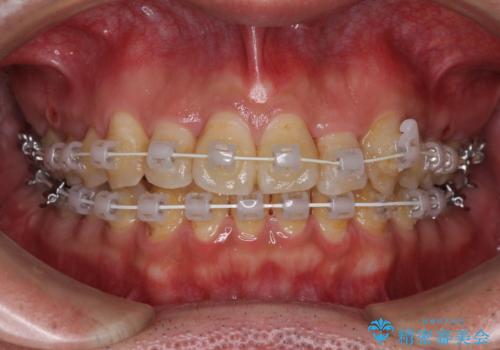

虫歯治療途中の歯は仮歯が装着されていたため、そのまま矯正治療を行い、矯正後に補綴治療を行うこととしました。

インビザライン矯正では苦手とする舌側転位した前歯をスムーズに改善することができました。